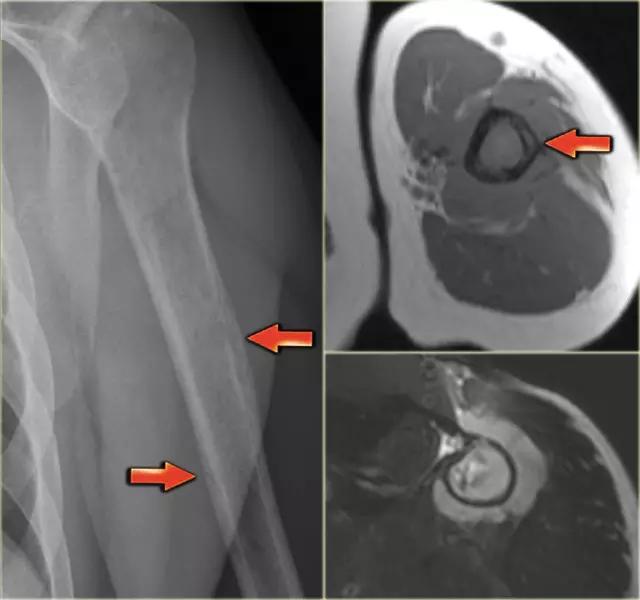

平片显示肱骨骨干的边缘欠清的溶解性病变。注意皮质骨的隧道(红色箭头)。在MR上注意到皮质骨和周围软组织块内的线性异常。鉴别诊断(取决于年龄):尤因氏肉瘤,骨髓炎和骨淋巴瘤。活检显示非霍奇金淋巴瘤